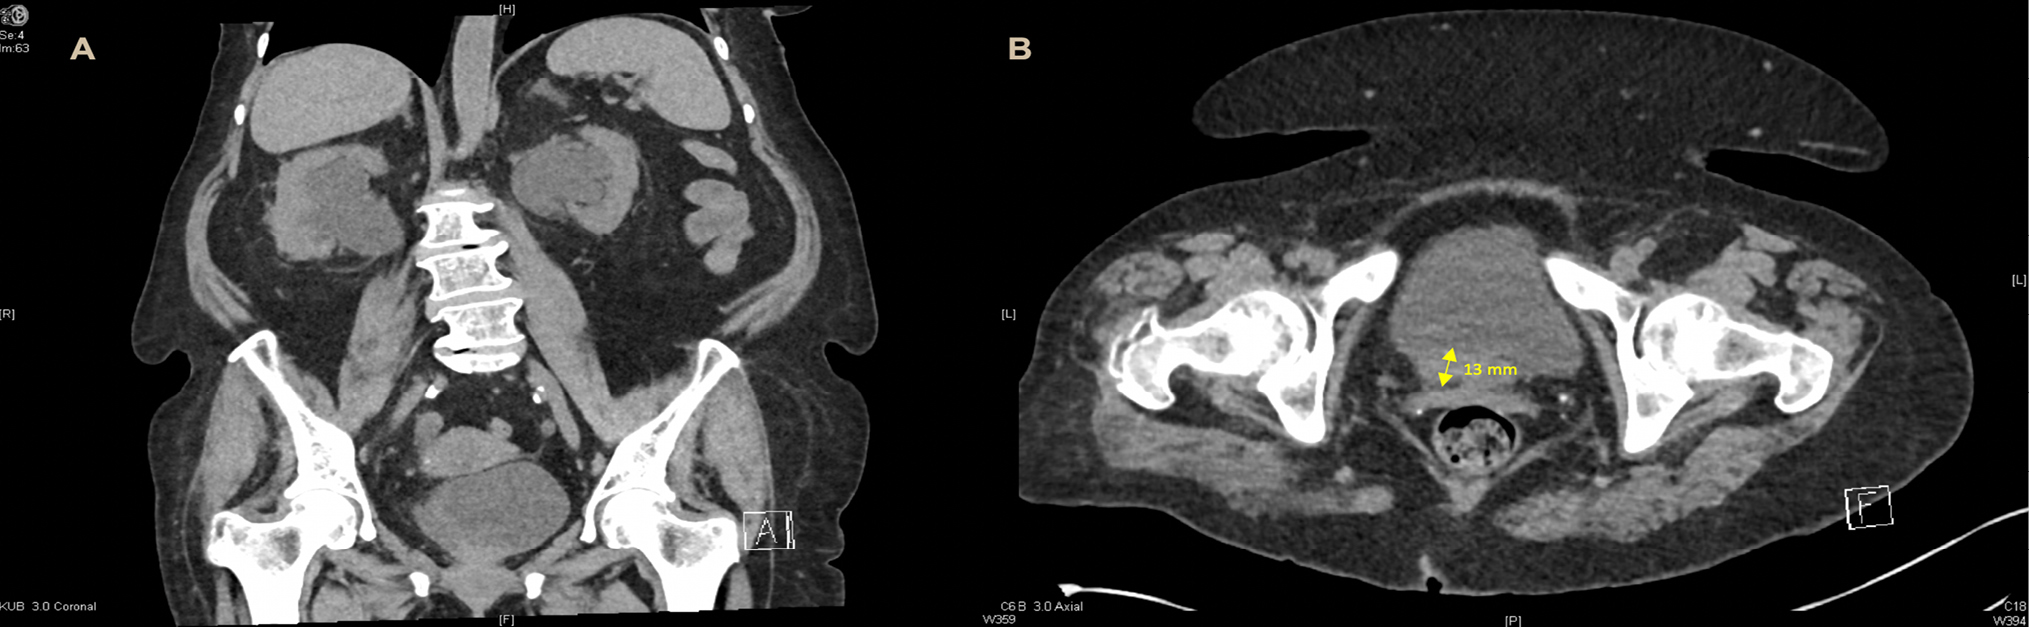

Intra-operatively a 5 cm polypoid mass with the appearance of muscle invasive bladder transitional cell carcinoma, invading both ureteric orifices was found on the trigone. Several smaller, multifocal satellite lesions situated on the lateral wall were identified. The tumor was resected uncovering both ureteric orifices. Retrograde pyelograms showed tortuous ureters with bilateral hydronephrosis and multiple filling defects (Fig. 2). Bilateral ureteric stents were placed. Resected tumor was sent for histopathological assessment and a staging CT of the chest and bone scan revealed no evidence of metastases.

Figure 2. Right retrograde pyelogram revealing multifocal filling defects within the right ureter (A) and right sided hydronephrosis with ureteric stent in situ (B).